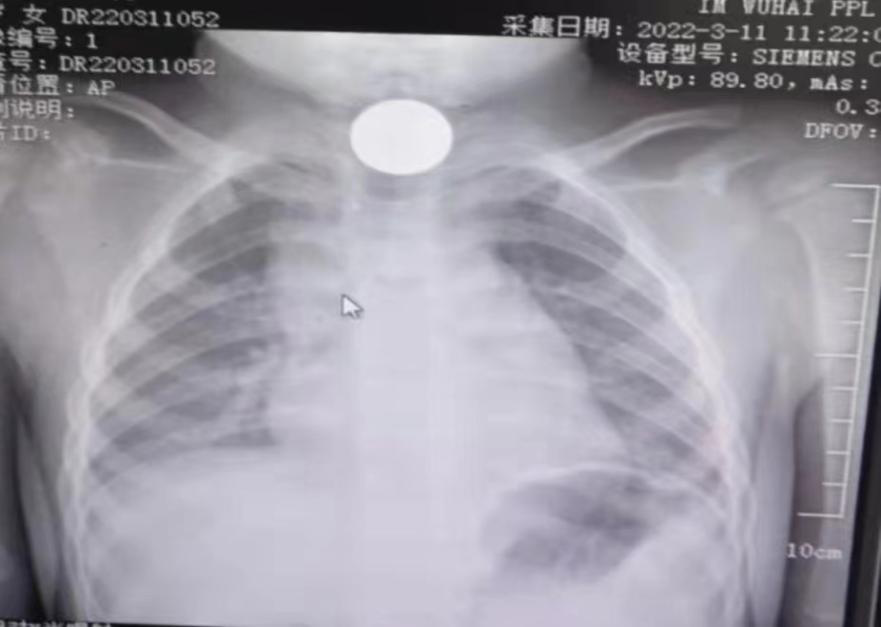

上午9时,一对年轻父母怀抱2岁小儿满脸焦急一路小跑来到乌海市人民医院儿科求医,周率主任医师接诊后见小儿有哭闹、流口水、抓挠喉咙、哽噎等症状,问询得知早起小儿玩耍时误食五角钱硬币,周率随即安排小儿前往影像科进行CT检查。影像结果可见食道上段第一个狭窄处卡有异物。由于硬币性质稳定且表面较为光滑,对食道粘膜和脏器损伤较小,如可以顺利掉入胃中便有可能随着胃肠蠕动排出。若不能顺利掉入胃中,只能通过胃镜将其取出。